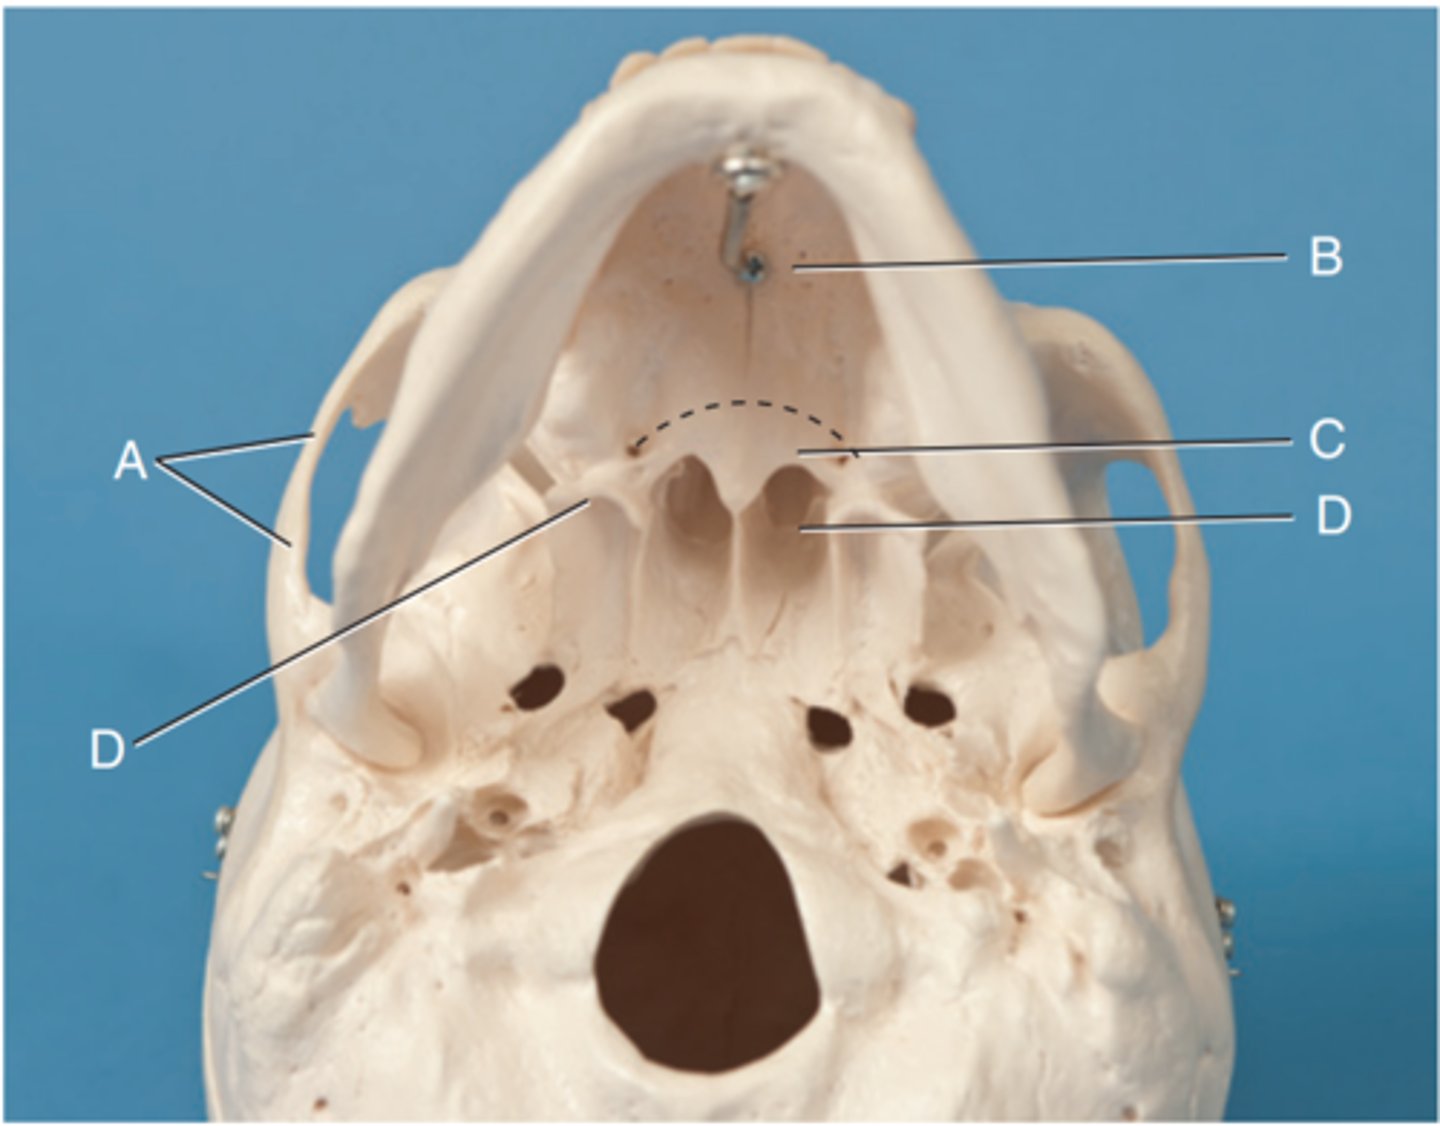

Label A

Posterior clinoid processes

Label B

Petrous ridge or petrous pyramid

Label C

Parietal bone

Label D

Occipital bone

Label E

Foramen magnum

Label F